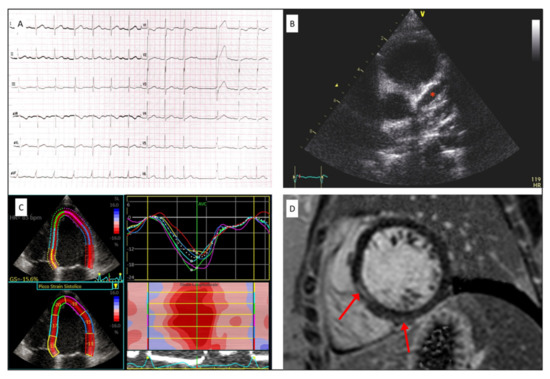

| EKG | |

| EKG abnormalities | 11 (48) |

| Ripolarization abnormalities | 8 (35) |

| Sinus bradycardia | 7 (30) |

| AV block | 2 (9) |

| ECHOCARDIOGRAPHY | |

| LVEF (%) | 59 ± 10 |

| GLS (%) | −17 ± 4.3 |

| E/A ratio | 1.9 ± 0.5 |

| Deceleration time (msec) | 147 ± 31 |

| Averaged E/e’ ratio | 8 ± 2.1 |

| TAPSE (mm) | 18.8 ± 4.7 |

| RV FAC (%) | 45 ± 7 |

| coronary dilatation | 6 (26) |

| coronary thrombosis | 1 (4) |

| pericardial effusion | 6 (26) |

| CARDIAC MRI (n = 17/23) | |

| LVEF | 60 ± 13 |

| LV edema | 1 (4) |

| LV LGE | 6 (26) |

| RVEF | 62.8 ± 3.9 |